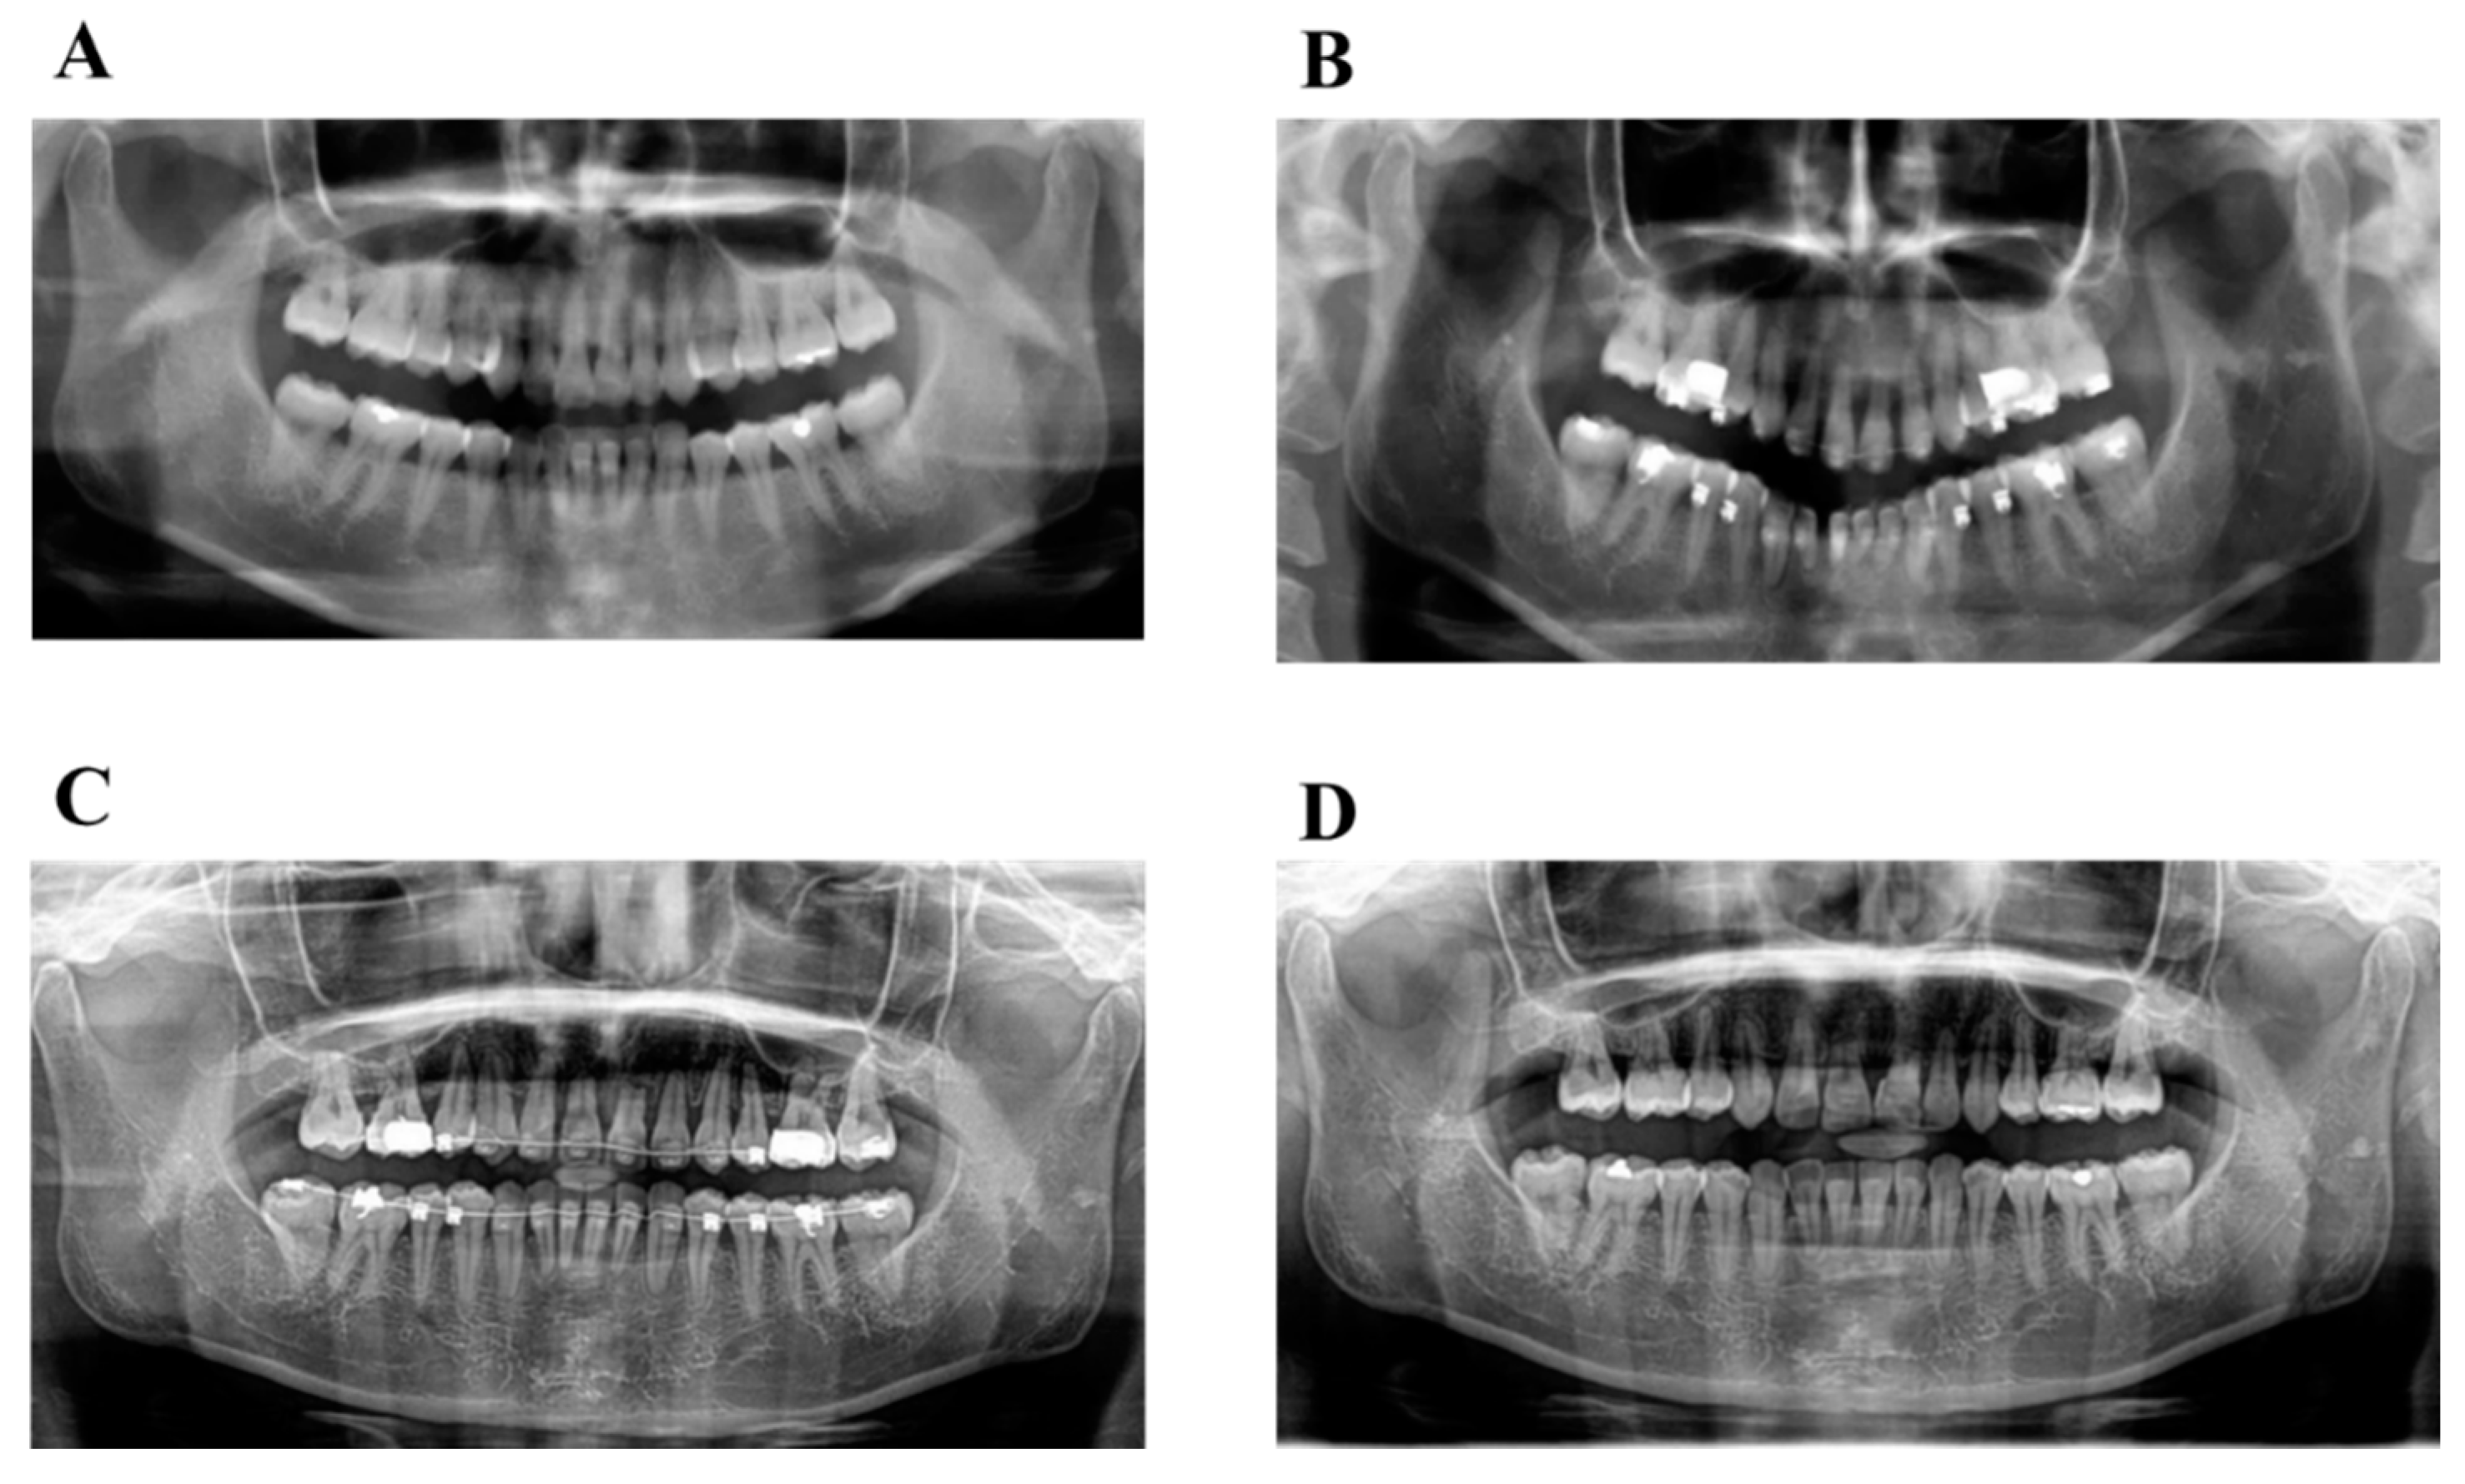

6.1. Diagnosis

6.2. Treatment Objectives

6.3. Treatment Alternatives

6.4. Treatment Progress

6.5. Treatment Results

6.6. Case Summary

| Measurement | Normal (Japanese Woman) | Pretreatment (29 y 19 m) | Posttreatment (31y 2m) |

|---|---|---|---|

| SNA (° ) | 81.3 ± 2.7 | 80.0 | 80.0 |

| SNB (° ) | 78.6 ± 2.7 | 79.5 | 79.0 |

| ANB (° ) | 2.6 ± 1.1 | 0.5 | 1.0 |

| FMA (° ) | 26.3 ± 4.1 | 24.0 | 24.0 |

| FMIA (° ) | 56.9 ± 6.4 | 52.0 | 61.0 |

| IMPA (° ) | 96.8 ± 6.4 | 104.0 | 95.0 |

| U1-FH (° ) | 112.1 ± 4.2 | 126.5 | 115.5 |

| U1-L1 (° ) | 123.5 ± 5.5 | 105.0 | 125.0 |

| U1-A-Pog (mm) | 6.2 ± 1.5 | 11.2 | 4.6 |

| L1-A-Pog (mm) | 3.0 ± 1.5 | 8.1 | 2.3 |

| Gonial angle (° ) | 118.8 ± 6.1 | 117.5 | 117.5 |

| E-line: Upper (mm) | 1.4 ± 2.0 | −0.5 | −2.0 |

| E-line: Lower (mm) | 1.4 ± 2.0 | +0.3 | −0.7 |